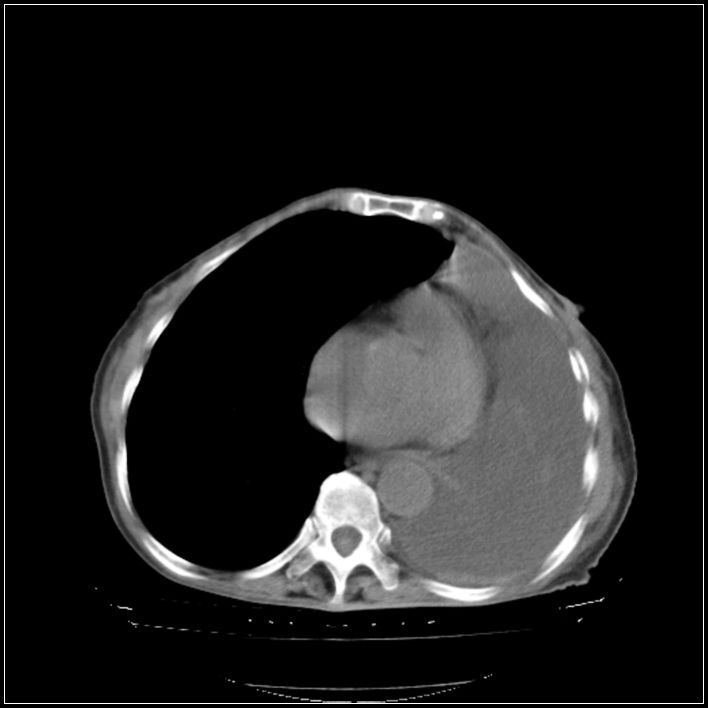

以下是引用ydx_74在2008-5-31 16:08:00的发言:[br]中心性肺癌并左侧肺不张、胸水。